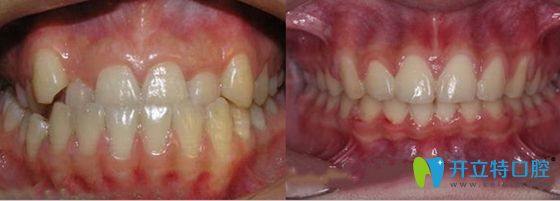

德正口腔的牙齒矯正價(jià)格給出了讓利,那效果怎么樣呢,一起來(lái)看看青少年反頜正畸案例效果:

鄭州德正口腔牙齒反頜正畸前后效果對(duì)比圖

【矯正方式】:金屬托槽正畸技術(shù);

【矯正效果】:這個(gè)孩子全程還是比較配合的,18個(gè)月時(shí)間完成矯正。牙齒反頜解除,咬合咀嚼功能良好,現(xiàn)正在佩戴保持器。